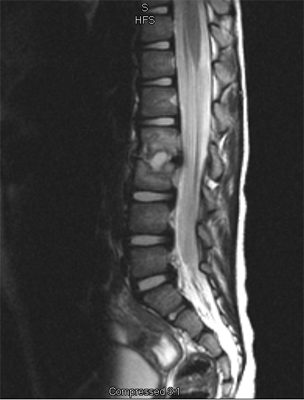

There are three general portions of the spinal column: The cervical or neck portion, the thoracic portion making up the mid-back, and the lumbar or lower portion. The lumbar portion connects with the pelvis at the sacrum.

There are specific curves associated with each region of the spine. When looking from the side, the cervical spine has an inward curve called a lordosis. The thoracic spine curves outward and is called a kyphosis, and the lumbar spine normally curves into the opposite way, creating a lordosis again. These three curves maintain balance of the spine in a forward and backward plane.

An MRI may be required if further examination of the spine is needed. An MRI machine uses magnetic waves, not X-rays, to show the soft tissues of the body. These tissues include the spinal cord, nerves, and discs. It can also evaluate spinal bones. An MRI allows your healthcare professional to look at slices of the area in question. The test may require the use of dye in an IV. Sedation or anesthesia may be needed to help your child lie still for this test.